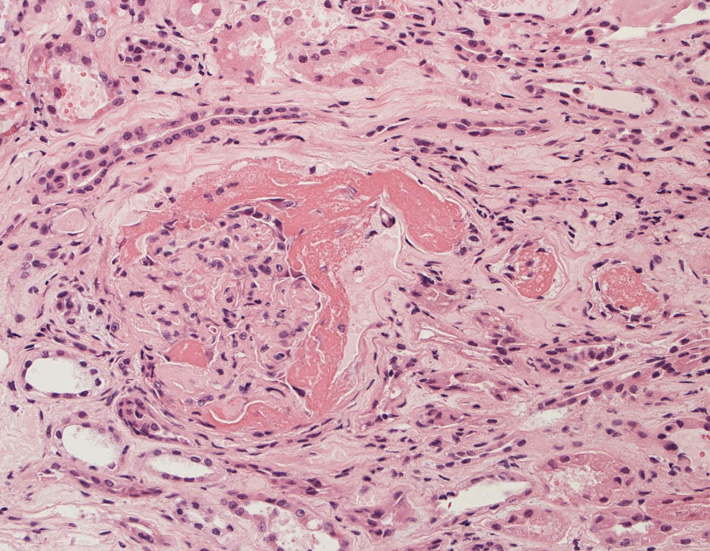

肺毛細血管炎 capillaritis

肺胞壁に多数の好中球浸潤。肺胞腔内に出血。 capillaritisが起こるWegener' granulomatosis劇症型には, なかなか肉芽腫性病変を見つけることは難しい

capillaritisの組織所見*17

Fig.01 capillaritisと肺胞出血Fig.02 Fig.01拡大像